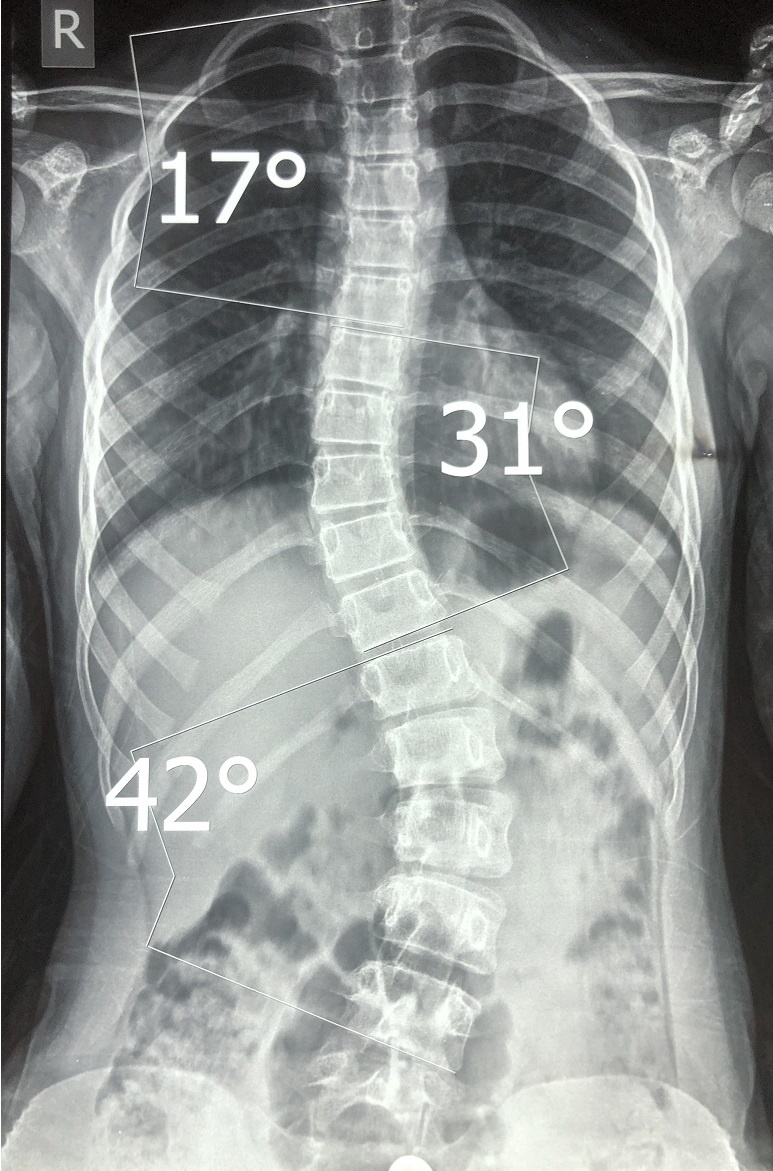

Схема анализа рентгеновского снимка для определения угла искривления разработана американским ортопедом Дж. Коббом (John Robert Cobb). Угол искривления, измеренный по рентгеновским снимкам, называется «углом по Коббу». Для определения угла деформации на переднезадней рентгенограмме проводят две линии, параллельные замыкательным пластинкам нейтральных позвонков. В точке пересечения этих линий измеряют угол сколиоза. Размер углов искривления позвоночника и степень сколиоза определяется несколькими методами (метод расчета Фергюссона, Кобба, Чаклина, Энчура, Абальмасовой). Рентгенологическая классификация сколиозов (по В. Д. Чаклину):

1 степень сколиоза. Угол сколиоза 1° - 10°

2 степень сколиоза. Угол сколиоза 11° - 25°

3 степень сколиоза. Угол сколиоза 26° - 50°

4 степень сколиоза. Угол сколиоза > 50° Величину искривления позвоночника можно зафиксировать и измерить с помощью рентгеновского снимка позвоночника у пациента в положении стоя. Возможны и врождённые реберные деформации и деформа

Рентгенограмма позвоночника прямая проекция. Сколиоз 3 степени по Чаклину.